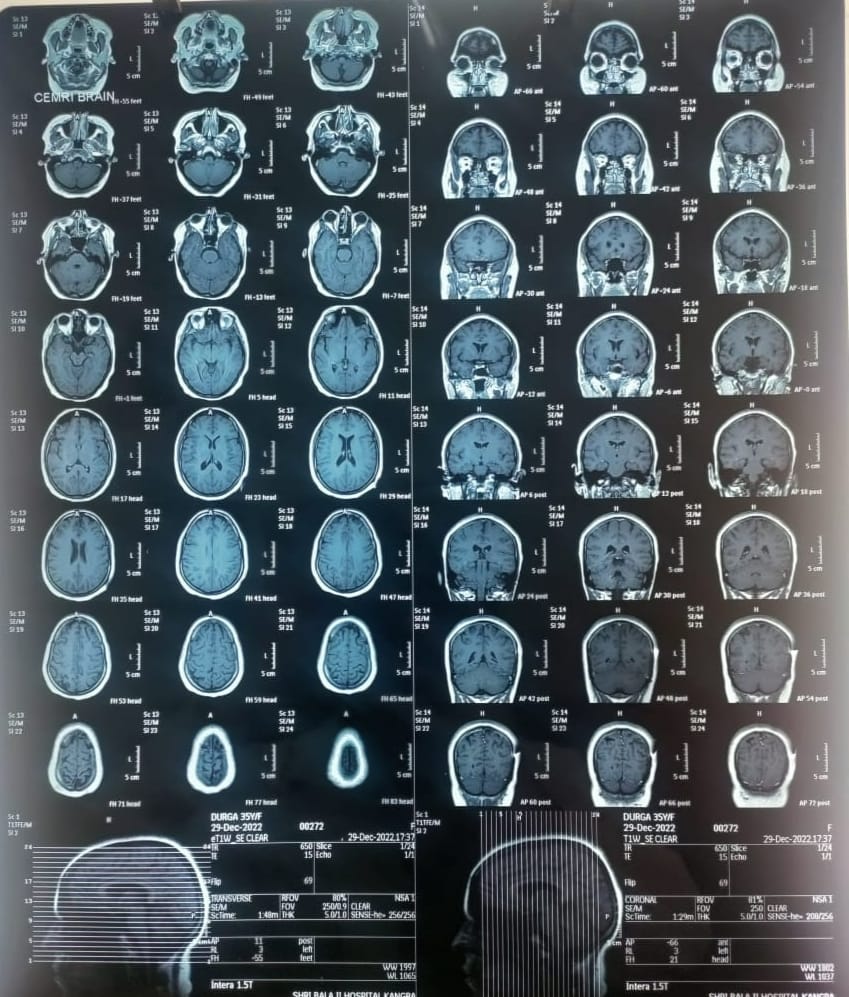

A 35 y old female presented to us with history of painless blurring of vision in right eye over one week. There was no history of pain, watering and redness. Patient denies consuming any undercooked pork, trauma to eye or any other similar episodes in past. At evaluation, BCVA in right eye was 6/6 p and left eye 6/6. Pupillary reactions was normal. Extraocular movements are full in all gazes. IOP was 16 mm of hg both eye. Anterior segment showed no abnormalities for both eye. Fundus examination revealed a oval translucent cyst of about 3 mm in diameter with pigment dusting its wall floating in the retina. Laboratory evaluation revealed a white cell count of 4.3x103/ul with normal eosinophil count. Hb was 14.3 g/dl and ESR was 15 mm/h. The patient was advised B scan, which revealed well-circumscribed round-shaped cystic lesion with thin echogenic wall in posterior vitreous along the retinal surface measuring approximately 2.7 x 2.3 mm in size. The lesion was seen on the temporal aspect of posterior surface at distance of approx. 2.2 mm from optic nerve. The patient had undergone a CT scan and MRI Brain in order to rule out the infection of CNS. CT scan and MRI brain was normal. Based on all, a diagnois of ocular cysticercosis was made.

Fig. 4: Normal MRI scan, which was done to rule out intracranial neurocysticercosis